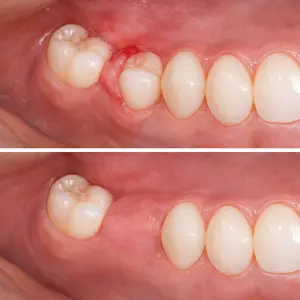

RESULTADOS REALES

Procedimientos

exitosos y controlados

Los procedimientos de cirugía oral permiten resolver problemas complejos y mejorar la salud oral del paciente.

Extracción dental

Paciente con diente no restaurable tratado mediante extracción.